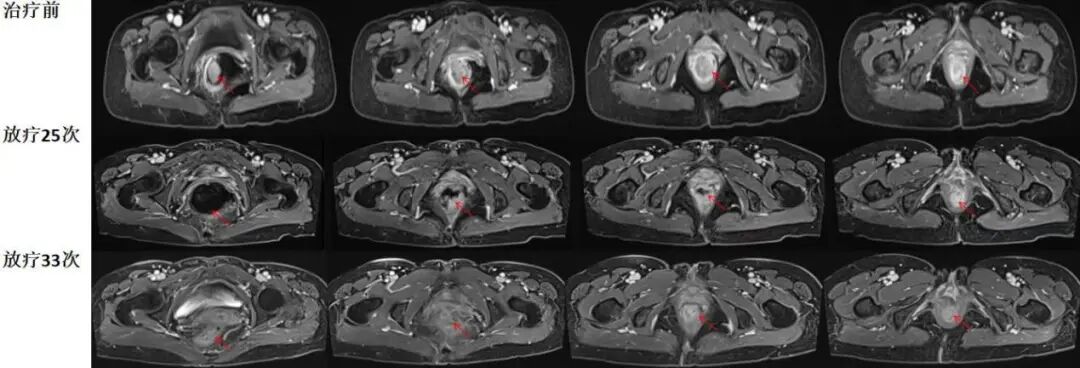

治疗近2周左右,患者便血症状逐渐减轻,随后消失。治疗5周后复查,可见肿物大部分消退,仅剩肛缘旁残留少许强化病灶。评估疗效,患者放化疗效果良好,进一步给予根治性放疗。

疗后复查,患者肿物完全消退,便血等症状消失。治疗过程顺利,没有发生明显副反应。尽管患者肿物紧邻膀胱,但没有发生放射性膀胱炎等并发症。

图注:放疗25次/5周复查可见,直肠内肿物显著缩退,直肠内仍有积气。治疗结束后复查可见,肿瘤病灶完全缩退,没有明显残留强化肿物,直肠内积气消失。